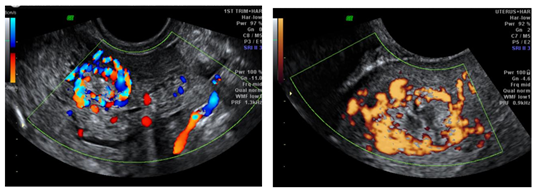

We report a rare case of intramyometrial ectopic pregnancy in a 27year old lady, P3L3 who presented to the emergency department at 8 weeks of gestation with complaints of pelvic pain and haemorrhage not subsiding with medical management. Transvaginal ultrasound revealed an exocentric gestational sac with thick decidua reaction and a “Ring of fire” appearance on color Doppler. Uterine cavity was empty and no adnexal masses visualized. Furthermore, MRI of the pelvis with contrast was done to confirm the location of the ectopic gestation which revealed a well defined T1 isointense T2 hyperintense lesion in the anterior myometrium abutting the junctional zone and showing contrast enhancement. Endometrial stripe was seen separately with an empty uterine cavity. Pouch of Douglas had no free fluid. On diagnostic laparoscopy, an asymmetrically enlarged swollen anterior wall of the uterus was seen. Hysteroscopy was performed concurrently demonstrating an empty uterine cavity. Medical management with methotrexate was initiated following confirmation of the diagnosis. Beta HCG at the time of diagnosis was 9949mIU/ml. She was followed up until the hormone levels returned to baseline and serial scans showed a healed solid collection (Figures 1‒7).

Figure 7 & 8 Color Doppler and power Doppler transvaginal ultrasound images showing “Ring of fire” appearance suggesting hypervascularity of the intramyometrial ectopic.

Pelvic pain and uterine bleeding in the presence of a positive pregnancy test are the hallmarks of an ectopic pregnancy. Early diagnosis of intramometrial gestation is very difficult and mostly made intraoperatively. Only three cases of intramural pregnancy have been correctly diagnosed preoperatively by ultrasound and one by magnetic resonance imaging.7 A gestational sac completely surrounded by myometrium is the typical ultrasound appearance of an intramural pregnancy. Ultrasound typically shows a gestational sac with thick decidual reaction with “Ring of fire” appearance suggesting hypervascularity, empty uterine cavity and no adnexal lesions. MRI confirms the location of the gestational sac and demonstrates no communication with the endometrial cavity and provides better visualization of the myometrium and endometrium separately. Some authors reported the use of hysteroscopy which allows direct visualization of the uterine cavity and tubal ostium and confirms the absence of the conceptus in the uterine cavity. Serial Beta HCG assay has been reported to be useful for the diagnosis.8